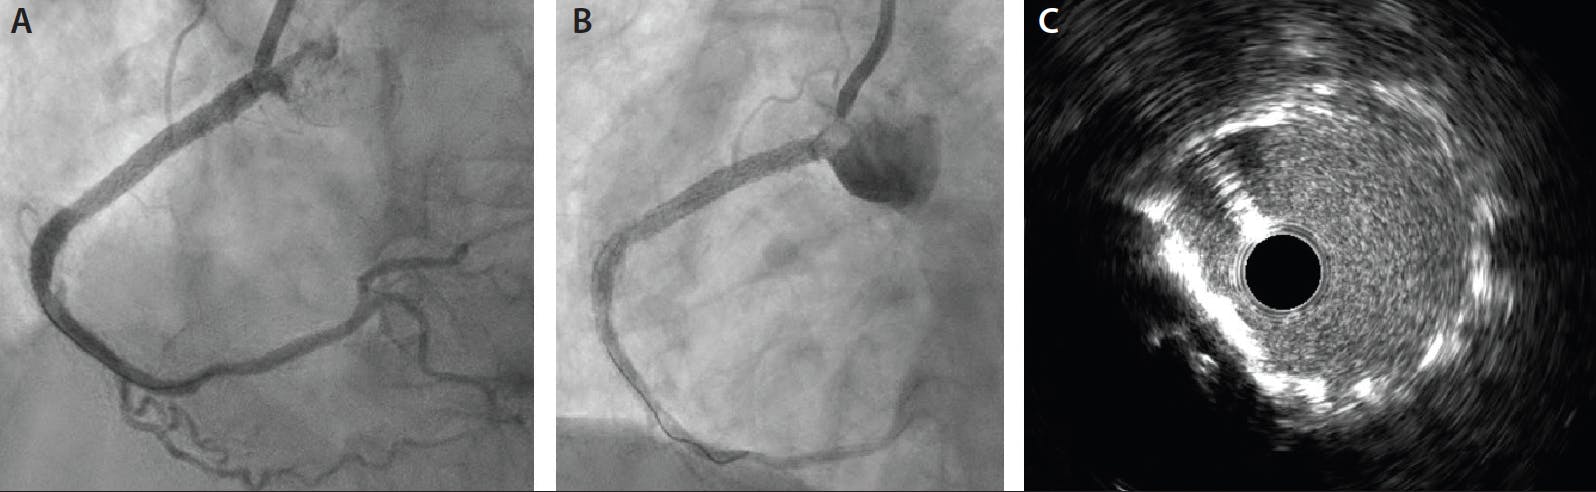

In the final step of the procedure, we employed IVUS for the MLD MAX post-PCI stent optimization assessment because we specifically wanted to interrogate the aorto-ostial stent coverage after Ostial FLASH treatment. Our decision to use IVUS rather than OCT was based on anticipated difficulty in completely clearing the aorto-ostial region of blood to enable OCT aorto-ostial overhang assessment. MAX assessment of the post-PCI result confirmed an optimized stent placement with no medial dissections at the distal stent edge, excellent stent strut-to-wall apposition, and 84% stent expansion. IVUS of the aorto-ostial segment also confirmed optimal lesion coverage with Ostial FLASH–induced flaring of the purposefully overhung stent (Figure 4C). The procedural execution resulted in improvement in the patient’s chest pain, normalization of her electrocardiogram changes, and excellent angiographic and intravascular imaging confirming the result without any complications (Figure 4A and 4B). The patient was treated with standard protocol dual antiplatelet therapy and was discharged on hospital day 2.

Figure 4. Final angiography and IVUS. Final angiography images (A, B). We employed IVUS for the MLD MAX post-PCI stent optimization assessment to interrogate the aorto-ostial stent coverage after Ostial FLASH treatment. MAX assessment of the post-PCI result confirmed an optimized stent placement with no medial dissections at the distal stent edge, excellent stent strut-to-wall apposition, and 84% expansion. IVUS of the aorto-ostial segment also confirmed optimal lesion coverage with Ostial FLASH–induced flaring of the purposefully overhung stent (C). Notable on IVUS, there is a slight “D” shape to the stent in the area where the calcific nodule was previously present (C).